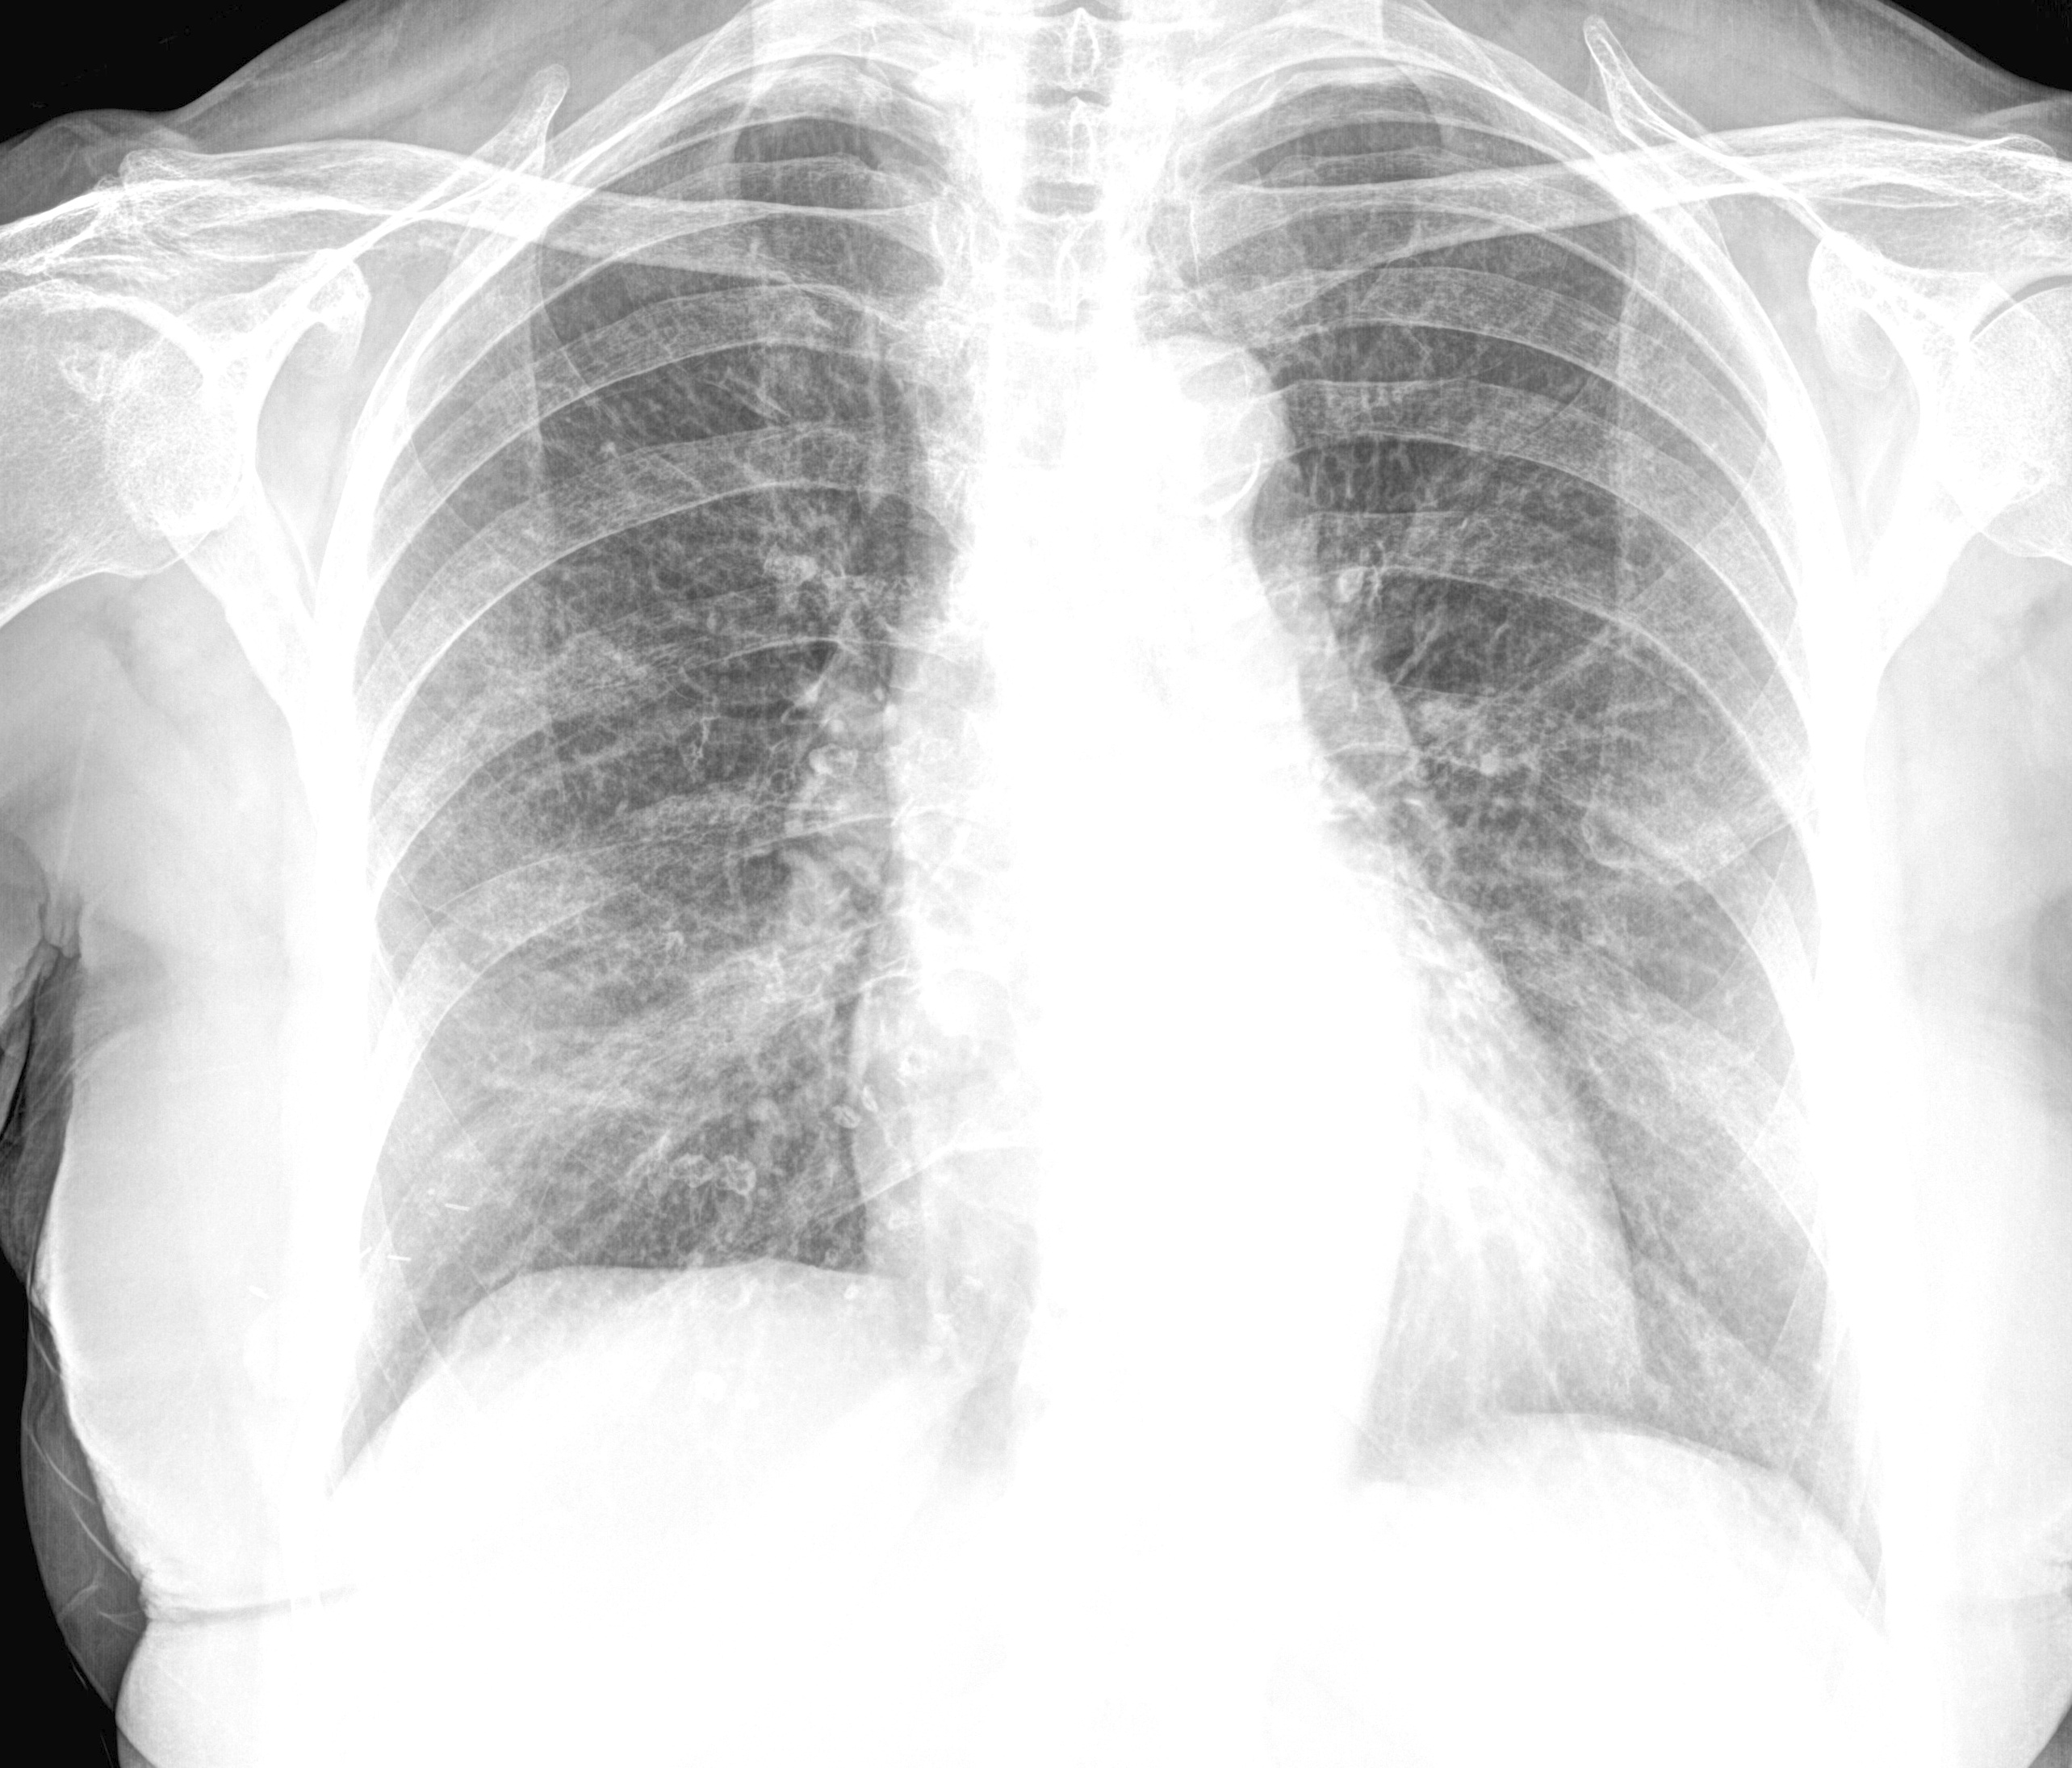

As highlighted in related work section 2, we found that many studies get healthy and pneumonia chest X-rays from the “Paul Mooney Pneumonia Detection Challenge” hosted at Kaggle kaggle:paul_mooney_chest_X-ray ; Kermany:Goldbaum:2018_identifying_medical_diagnosis . This dataset have chest X-rays which were selected from retrospective cohorts of pediatric patients of one to five years old from Women and Children’s Medical Center, Guangzhou, China. This dataset has three classes, namely, Normal, Bacterial Pneumonia, and Viral Pneumonia. The normal chest X-ray depicts clear lungs without any areas of abnormal opacification in the image. Bacterial pneumonia typically exhibits a focal lobar consolidation, whereas viral pneumonia manifests with a more diffuse “interstitial” pattern in both lungs. Figure 4 shows random sample of each of the three classes and a random sample from the curated COVID-19 dataset.

Refer to caption

(a) Normal (paediatric patient)

(b) Bacterial pneumonia (paediatric patient)

(c) Viral pneumonia (paediatric patient)

(d) COVID-19 (Adult)

Figure 4: Differences in chest X-rays from paediatric patients vs. COVID-19 chest X-ray from adult population.

From a radiologist’s perspective, there are key differences between chest X-rays captured from paediatric patients and adult population. First, the size of children’s chest is small compared to adult’s chest, which can also be visible in Figure 4. Second, the rib of children are positioned more horizontally than those of adults as can be seen in Figure 5. Given that children and infants differ, both anatomically and physiology, from adults, these differences have an impact on the clinical assessment using chest X-rays. A learning algorithm can learn these key differences between paediatric population and adult population based on the chest X-rays, leading to model bias as model can report results solely based on these differences rather than radiographic features of a particular disease or abnormality. Hence, we hypothesise not to train model having chest X-rays from mix of both children and adult population. To prove our hypothesis, we run additional experiments to classify COVID-19 vs. Normal (healthy) cases by taking normal cases from different sources. Table 6 shows distribution of normal and COVID-19 cases for binary classification under two settings. For each of the two settings, we split data for each class into training (1106 images), validation (158 images), and testing (316) images, making in total 1580 chest X-rays.